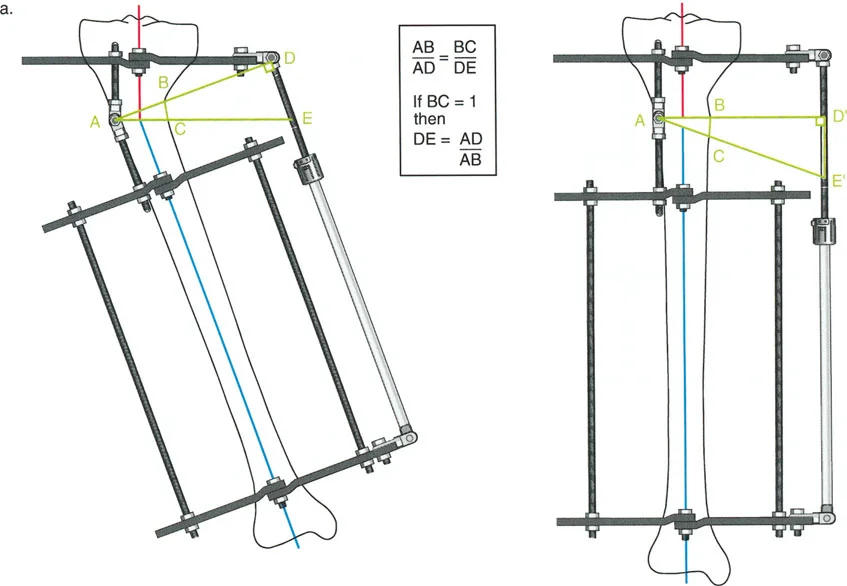

إتقان معدلات الشد: قاعدة المثلثات المتشابهة

القاعدة الذهبية البيولوجية لتوليد العظم بالشد، التي وضعها إليزاروف بعد عقود من التجارب على الحيوانات والبشر، هي معدل شد يبلغ 1 ملم يوميًا. يتم تقسيم هذا عادة إلى زيادات قدرها 0.25 ملم كل 6 ساعات لمحاكاة النمو المستمر للوحة النمو.

ومع ذلك، فإن الخطأ الشائع، الذي قد يكون كارثيًا أحيانًا للجراحين المبتدئين، هو سوء فهم أين يجب أن يحدث هذا الـ 1 ملم يوميًا.

معدل 1 ملم/يوم ينطبق بشكل صارم على القشرة المقعرة للعظم في موقع قطع العظم (الحافة الأمامية للإسفين المفتوح). نظرًا لأن الجهاز (قضيب الشد أو دعامة TSF) يقع على مسافة من العظم، خارج غلاف الأنسجة الرخوة، فإنه يتحرك على طول قوس أكبر بكثير. إذا وجهت المريض لشد القضيب بمعدل 1 ملم يوميًا، فإن العظم الفعلي سيُشد بجزء ضئيل من هذا المعدل، مما يؤدي إلى التصلب المبكر لموقع قطع العظم.

حساب معدل الشد الحقيقي

لحساب المعدل الصحيح للشد عند المفصلة، نستخدم قاعدة المثلثات المتشابهة، والتي تعتمد أساسًا على القاعدة الهندسية للدوائر متحدة